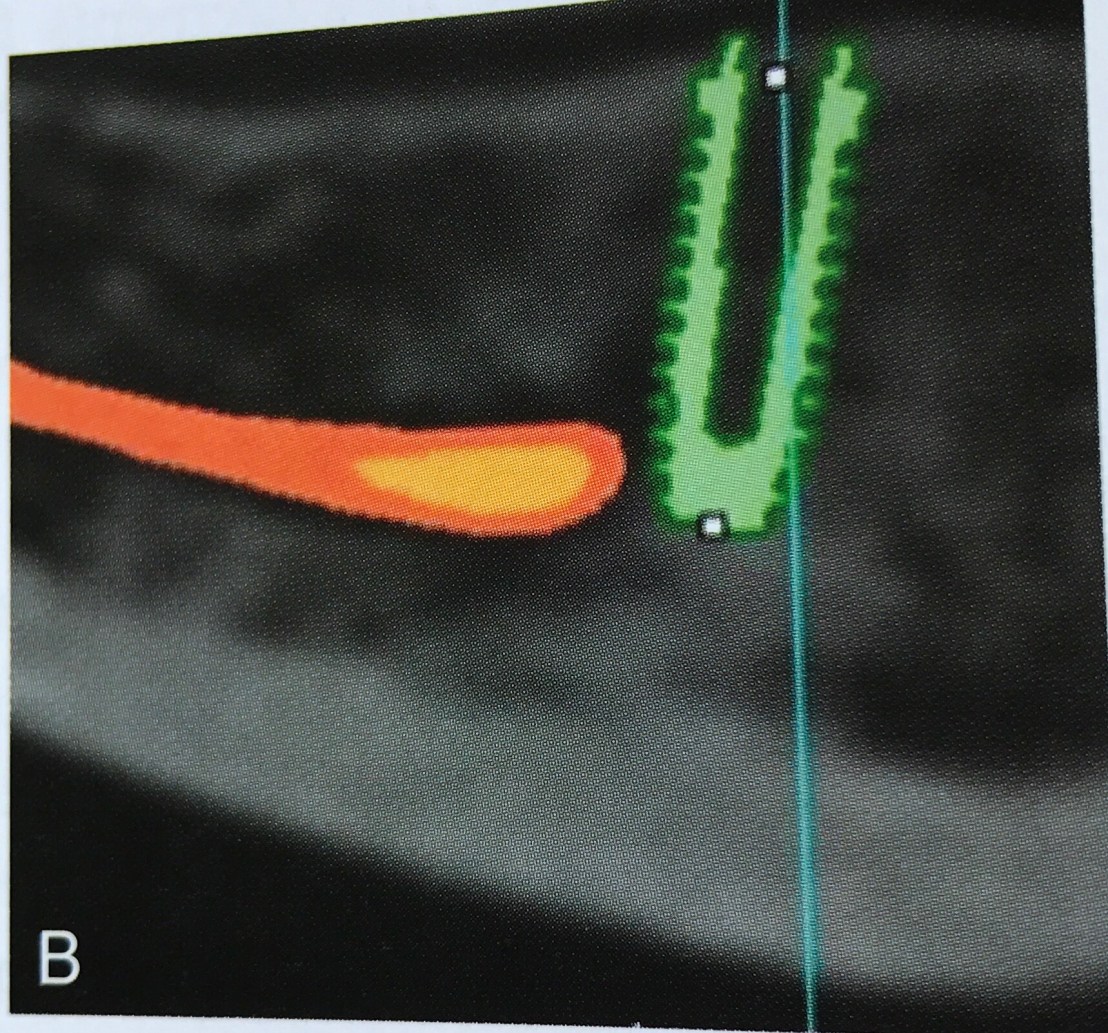

Film แสดงการวางตำแหน่ง Implant ที่ลึก (เทียบระดับ CEJ) และปลายที่รบกวน Mand canal

ถ้ามอง Cross section view ในรูป B รูเปิดที่เห็นด้าน buccal นั่นคือ Mental foramen ครับ

รูป E ภาพ CBCT แสดงการยืนยันชัดเจน